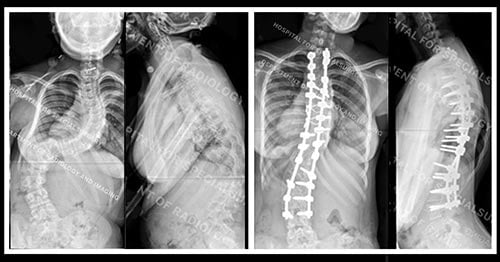

Deformity Correction

Deformity correction is the surgical adjustment or modification of bone that grows incorrectly as the result of a disease or condition, such as bowlegs or knock knee. Spinal deformity correction surgery can be used to help patients with scoliosis, kyphosis, trauma, or other conditions that affect the spine, such as ankylosing spondylitis. Corrective surgery may also be used for conditions in which the hands, fingers, arms, legs, knees or ankles grow at incorrect angles or lengths. See also Limb Lengthening Surgery.